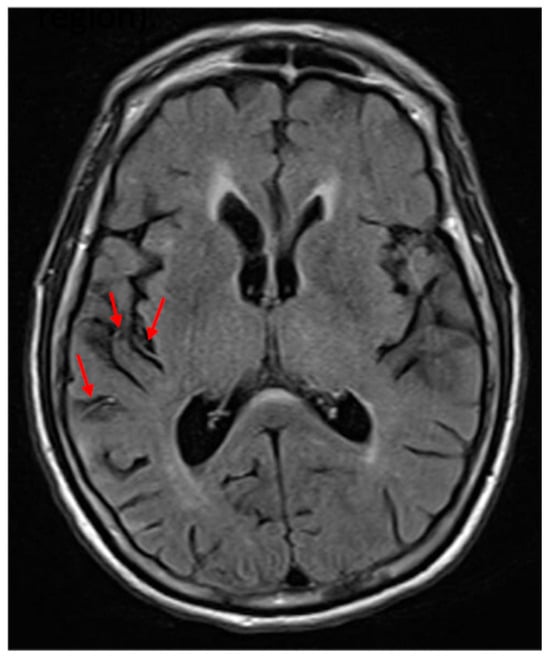

Each participant completed a neglect task with 30 ovals: 10 full, 10 with a gap on the left, and 10 with a gap on the right (adapted from Ota). Participants were asked to circle full ovals and cross out ovals with a gap on either side. We defined VCN as >10% of the total number of ovals left unmarked after the most extreme mark on the contralesional side (Figure 2) and SCN as incorrectly marking >10% of contralesional gaps (Figure 3). All participants completed neglect testing and brain MRI within 5 days of stroke onset.

Figure 2. Example of left viewer-centered neglect (VCN). Participants were asked to circle full ovals and cross out (put an X on) ovals with a gap on either side. The yellow highlighted items indicate errors. Errors were stimuli that the patient failed to mark at all.